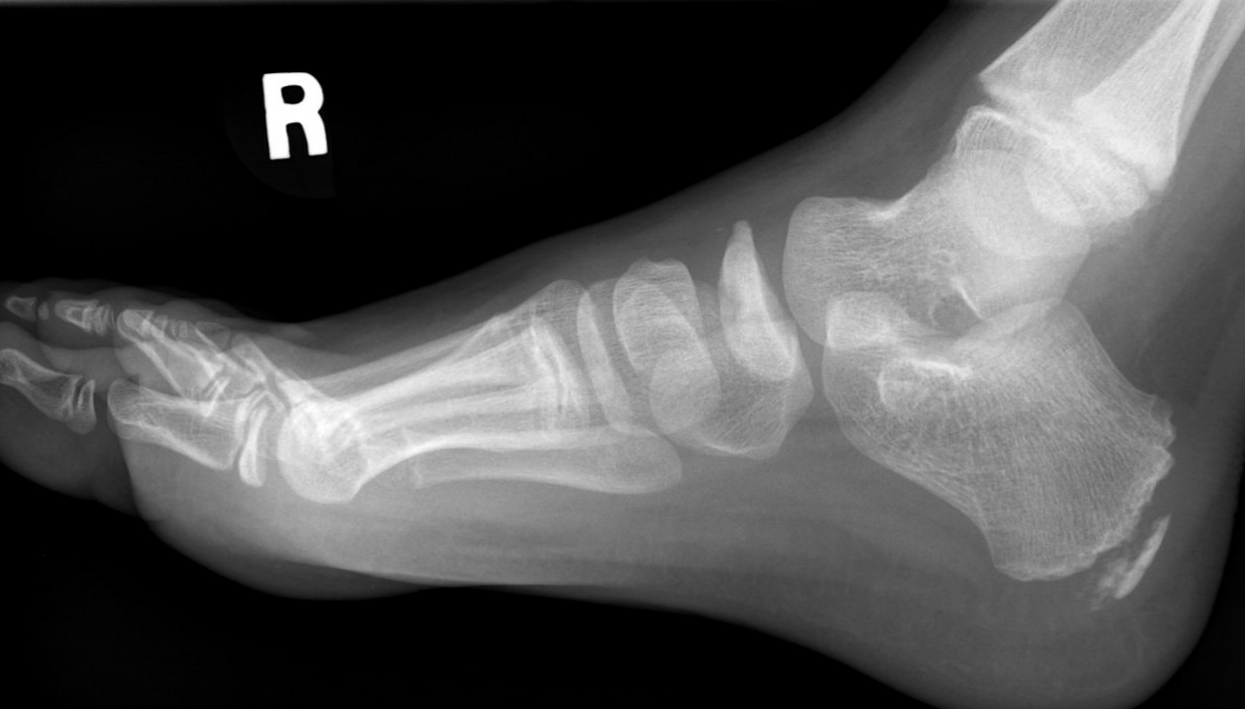

X-ray

Flattening / sclerosis / fragmentation of navicular